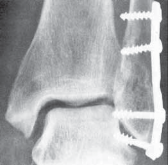

TECHNIQUES B TECH FIG 5 • Direct posterior plating is well

---

C

suited for fractures involving large portions of the posterior malleolus.

A.

Postreduction lateral radiograph showing a posterior malleolus fracture involving more than one third of the articular surface.

B.

Patient in prone position, incision between Achilles and posterior fibula border.

C.

Access is via the interval between the flexor hallucis longus and the peroneal muscle belly. D. Posterior malleolar fragment following A D fibular plating. POSTERIOR MALLEOLUS FIXATION 1. If an adequate reduction can be achieved via closed, indirect reduction, the fracture can be stabilized with cannulated lag screws placed in the anterior-to-posterior direction.

--- TECH FIG 6 • Postoperative AP and lateral radiographs demonstrating posterior plating of the tibia to buttress the posterior malleolar fracture fragment. ### TECHNIQUES